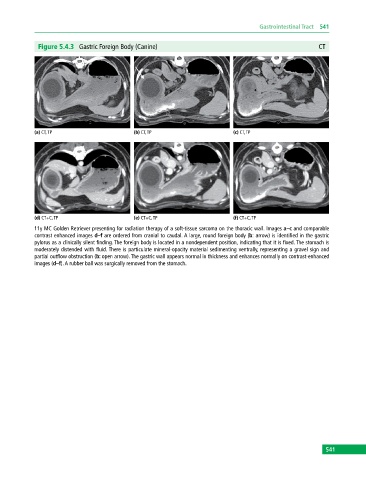

Figure 5.4.3 Gastric Foreign Body (Canine) CT

11y MC Golden Retriever presenting for radiation therapy of a soft‐tissue sarcoma on the thoracic wall. Images a–c and comparable

contrast enhanced images d–f are ordered from cranial to caudal. A large, round foreign body (b: arrow) is identified in the gastric

pylorus as a clinically silent finding. The foreign body is located in a nondependent position, indicating that it is fixed. The stomach is

moderately distended with fluid. There is particulate mineral‐opacity material sedimenting ventrally, representing a gravel sign and

partial outflow obstruction (b: open arrow). The gastric wall appears normal in thickness and enhances normally on contrast‐enhanced

images (d–f). A rubber ball was surgically removed from the stomach.